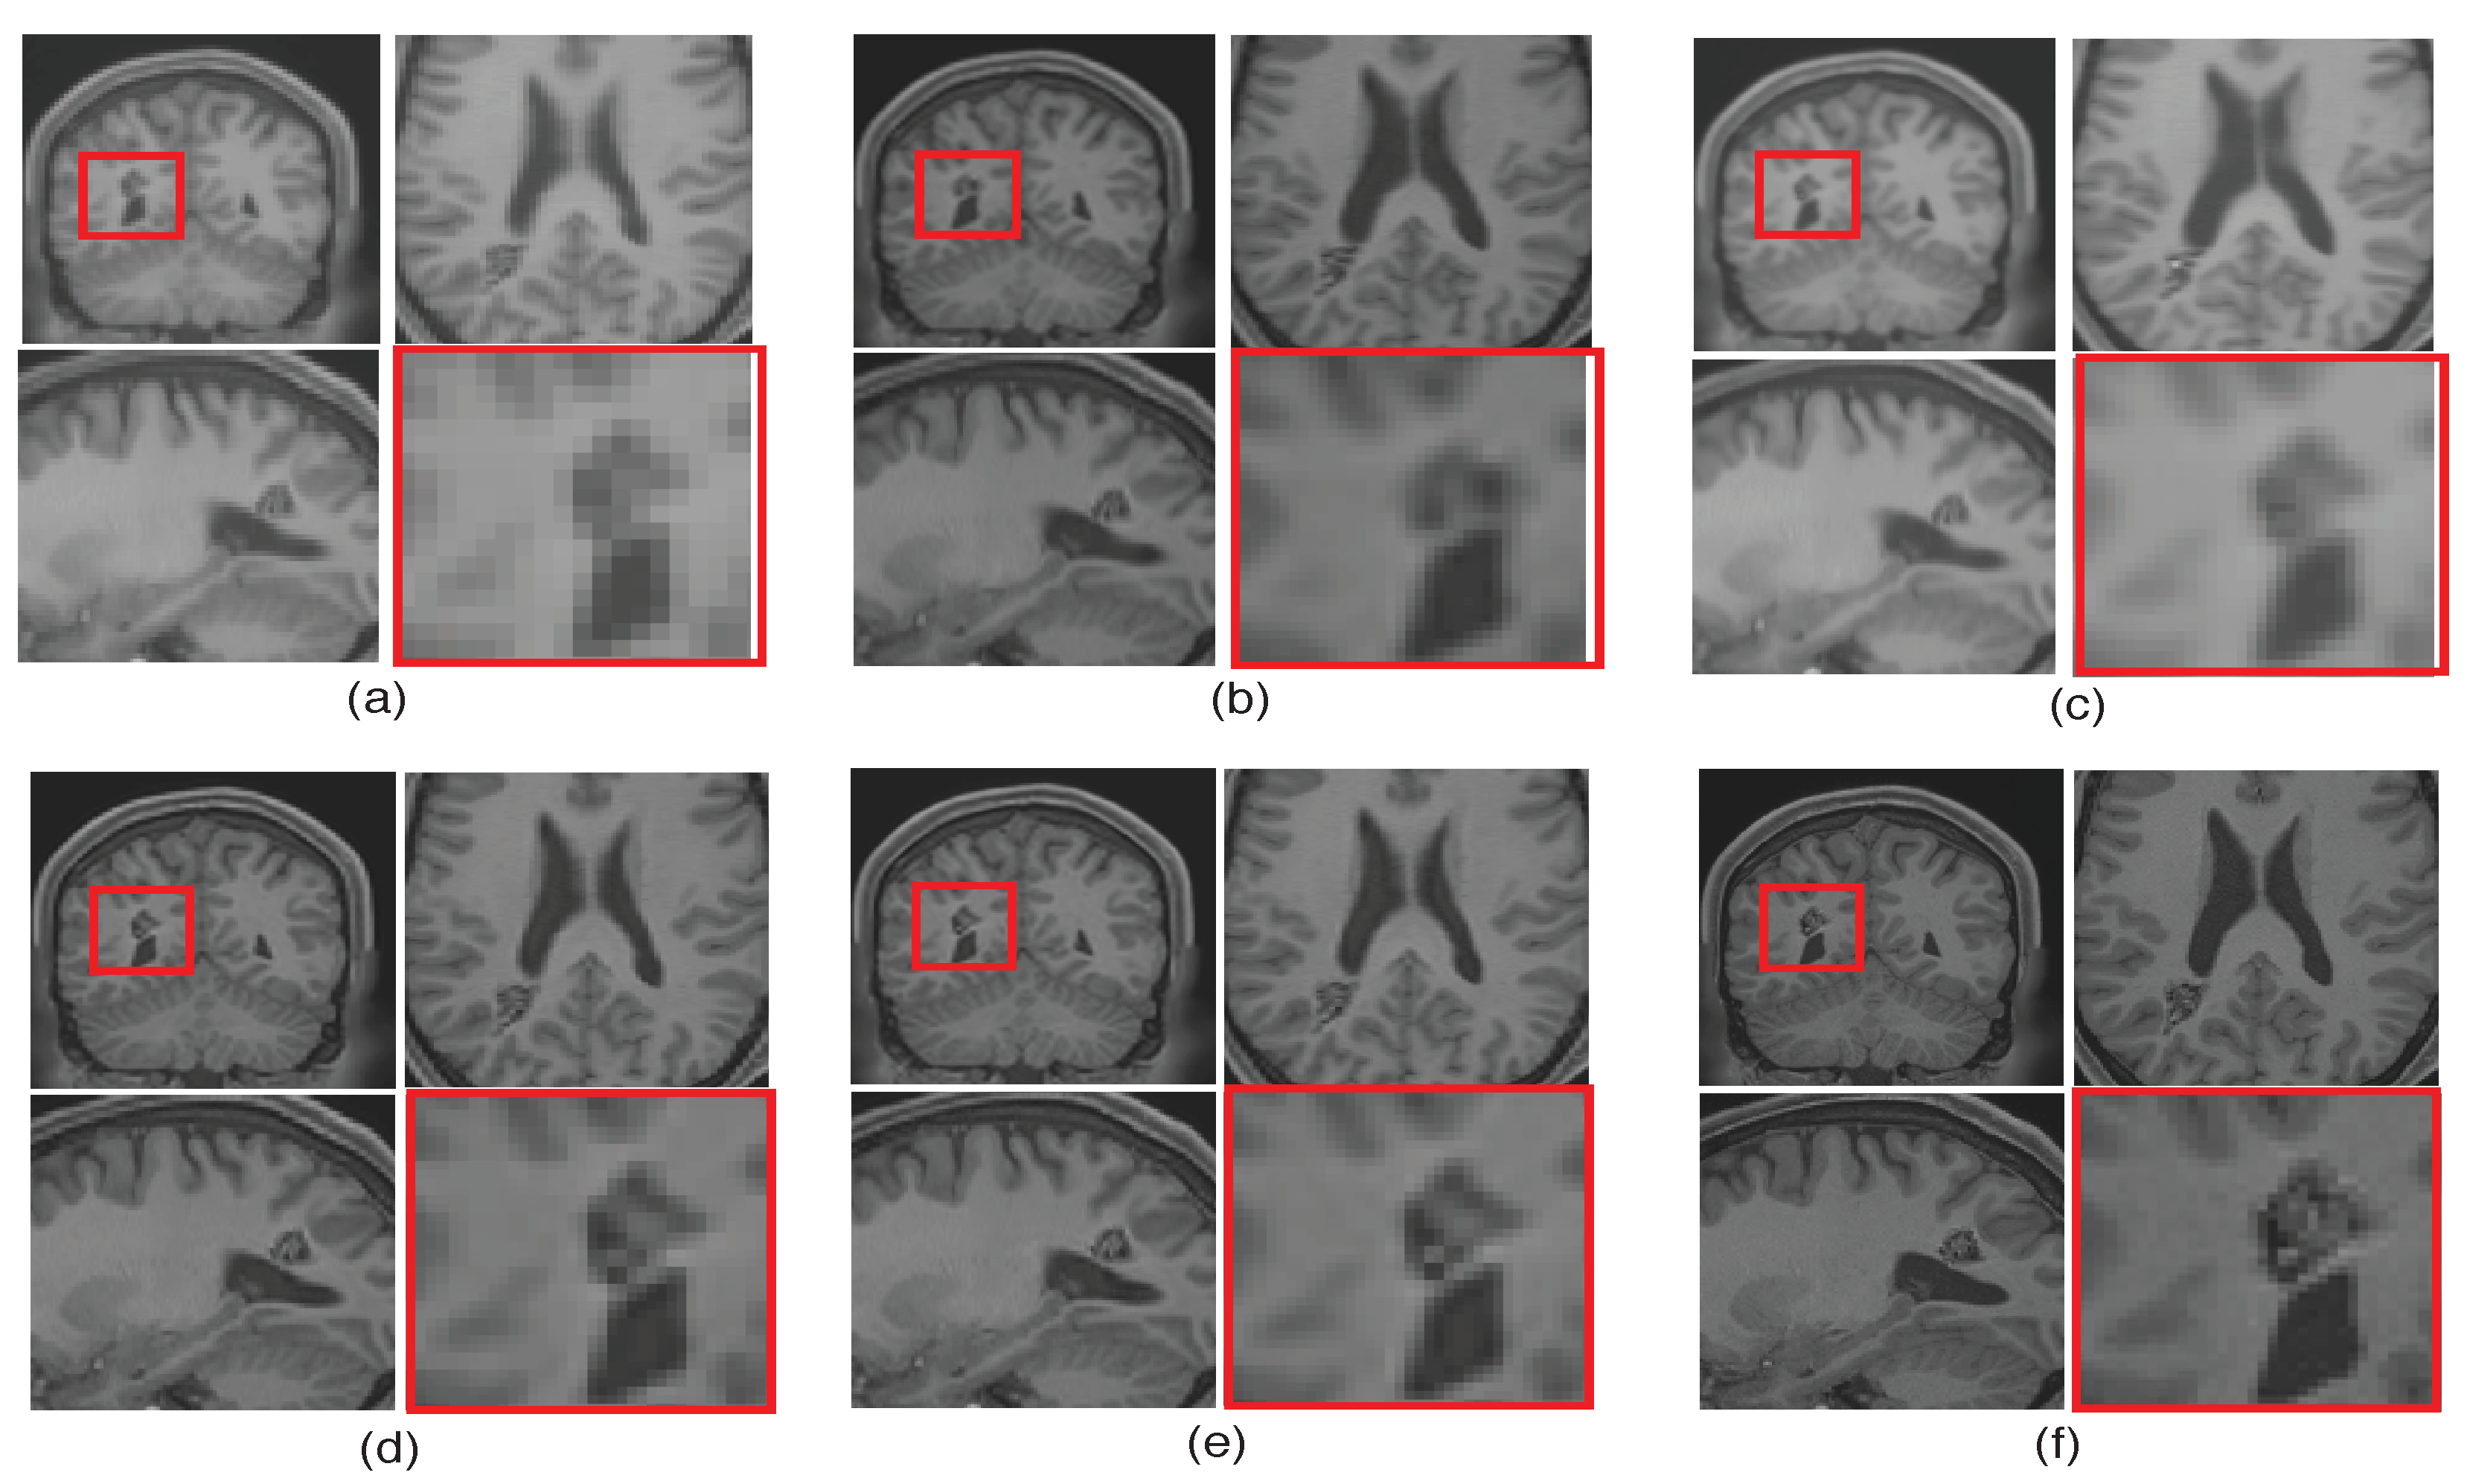

The performance of the proposed single framework for the super resolution of noisy MR images has been evaluated here for 2% Gaussian noise and different upsampling factors. For existing SR methods, the images are first denoised using AONLM [40]. The qualitative results using different algorithms for upsampling a randomly selected noisy image by factor 2 are shown in Figure 13. To illustrate the significance of the proposed approach for efficient denoising as well as the preservation of image details, different kinds of regions are zoomed and shown separately. The green box in Figure 13 comprises the region with strong edges, the red box shows the region with minor edges and texture, and the cyan box shows the smooth region. It can be observed that the reconstructed image using spline interpolation and the non local means in three dimensions (NLM3D) approach in Figure 13b,c blur the image details in every kind of region and hence provide poorer contrast but with better denoising in each region. The LRTV method, however, tends to provide better contrast among tissues and preservation of image details, yet it is not able to provide efficiently denoised smooth regions (see red and cyan boxes in Figure 13d). The proposed work, on the contrary, can be observed to reconstruct strong edges while preserving the image details with limited noise (see green box Figure 13e), it can relatively better suppress the noise in patches with smooth and texture/minor edges as compared to LRTV [12] (can be seen in red and cyan boxes), and it can provide improved contrast as compared to NLM3D [13]. It demonstrates that the proposed method tends to improve the trade-off between the preservation of image details and suppression of noise. The obtained PSNR, SSIM, and FSIM values for different subjects are summarized in Table 3 and show that the proposed work performs relatively better than existing unsupervised methods when combined with supervised denoising method.

Figure 13.

Demonstration of reconstruction quality of different kinds of regions/patches, region with edges (green boxes), region with texture (red boxes), and smooth region (cyan boxes), after super resolving real MR images degraded with downsampling factor 2 and 2% noise, using different algorithms. (a) NN interpolation of noisy LR image, (b) spline interpolation of denoised LR image, (c) NLM3D [13] applied on denoised LR image, (d) LRTV [12] applied on denoised LR images, (e) the proposed work applied on a noisy LR image, and (f) the original noise-free HR image.